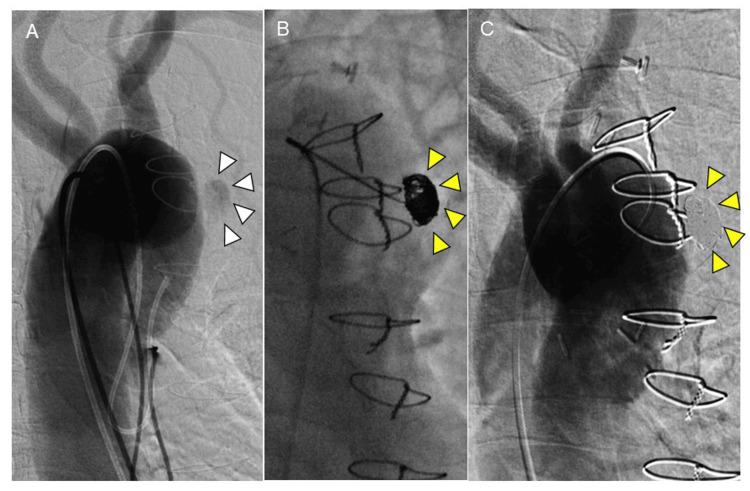

Ulcer-like projections (ULPs) with a tendency to enlarge are at risk of aortic events such as new dissection, aneurysmal formation, or rupture and require therapeutic intervention. However, what should be done after open chest surgery when standard thoracic endovascular aortic repair (TEVAR) cannot be performed is debatable. Here, we present a case of coil embolization of a newly enlarged ULP that was not amenable to TEVAR following a hemiarch aortic arch repair. A 68-year-old male with a history of ascending and hemiaortic arch repair for acute type A aortic dissection presented with a chief complaint of chest pain three months prior to presentation. A post-type A dissection ULP remained in the aortic arch but had enlarged over the three months. Therapeutic intervention was planned to avoid aortic events; however, standard and fenestrated TEVAR were going to be anatomically challenging. Since the patient was in poor general condition after diverticulitis and stroke, reopened total arch replacement and total debranching TEVAR were avoided. The neck of the ULP was narrow and had a small volume; therefore, we assessed that the coil-packing method could embolize the ULP. Coil embolization was successful, and the patient had no postoperative complications. A computed tomography scan at the remote stage showed no recanalization or enlargement, and the patient was stable. Coil embolization may be attempted for arch ULP that can enlarge if the ULP can be embolized with intra-aneurysmal packing when it is difficult to perform a reopen surgery or TEVAR, including standard zone II, total debranching, and fenestrated TEVAR.

具有扩大倾向的溃疡样突出(ULP)有发生主动脉事件的风险,如新发夹层、动脉瘤形成或破裂,需要进行治疗干预。然而,在开胸手术后无法进行标准胸主动脉腔内修复术(TEVAR)时应采取何种措施仍存在争议。在此,我们报告一例在半弓主动脉弓修复术后,对一个新增大的、无法进行TEVAR的ULP进行弹簧圈栓塞的病例。一名68岁男性,有因急性A型主动脉夹层进行升主动脉和半弓主动脉弓修复的病史,在就诊前三个月因胸痛为主诉前来就诊。A型夹层后残留的ULP位于主动脉弓,但在三个月内有所增大。计划进行治疗干预以避免主动脉事件;然而,标准和开窗TEVAR在解剖学上具有挑战性。由于患者在患憩室炎和中风后全身状况较差,避免了再次进行全弓置换和全去分支TEVAR。ULP的颈部狭窄且体积小;因此,我们评估弹簧圈填充法可栓塞ULP。弹簧圈栓塞成功,患者术后无并发症。远期计算机断层扫描显示无再通或增大,患者情况稳定。对于难以进行再次手术或TEVAR(包括标准II区、全去分支和开窗TEVAR)的、如果ULP可通过瘤内填充进行栓塞且可能增大的弓部ULP,可尝试弹簧圈栓塞。